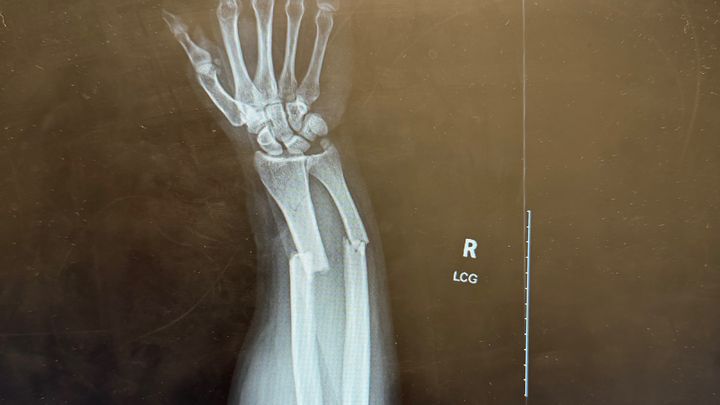

Our friend Rigo was injured during an indoor soccer game on Monday. In a split second, a powerful shot sent the ball flying toward him, and as he tried to protect his face, it struck his right hand with such force that both bones snapped. The injury was severe, and Rigo needed immediate medical attention, including surgery, an ER visit, and an ambulance ride.

Nuestro amigo Rigo se lesionó durante un partido de fútbol sala el lunes. En una fracción de segundo, un potente disparo envió el balón volando hacia él y, al intentar protegerse la cara, le impactó la mano derecha con tanta fuerza que le rompió ambos huesos. La lesión fue grave y Rigo necesitó atención médica inmediata, que incluyó cirugía, una visita a urgencias y un traslado en ambulancia.